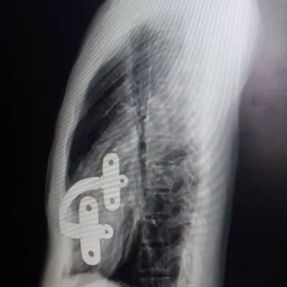

The patient’s anterior chest wall exhibits a prominent depression deformity,characterized by a horizontal groove that affects both sides of the anterior chest wall. There is a surgical scar along the midline and one on the left side, with two scars visible on the right side of the chest wall. A 4x4 cm mass is located on the left chest wall, characterized by darkened skin and noticeable fluctuation upon palpation. The mass extends deep into the intercostal space. Mild scoliosis is also observed. The patient was ultimately diagnosed with grooved chest.

2. Improper bar Placement and Positioning: Preoperative imaging reveals that the bar was positioned along the upper edge of the groove-like depression and was placed at an angle.For optimal support and effective correction of the depressed bony structure, the bar should have been positioned at the base of the depression.